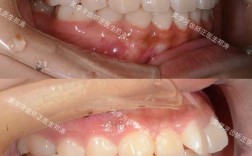

- 临床经验:关注医生从事正畸工作的年限(建议5年以上)、案例数量(尤其是复杂病例,如骨性错颌、埋伏牙等),可通过机构官网、社交平台查看真实案例对比;